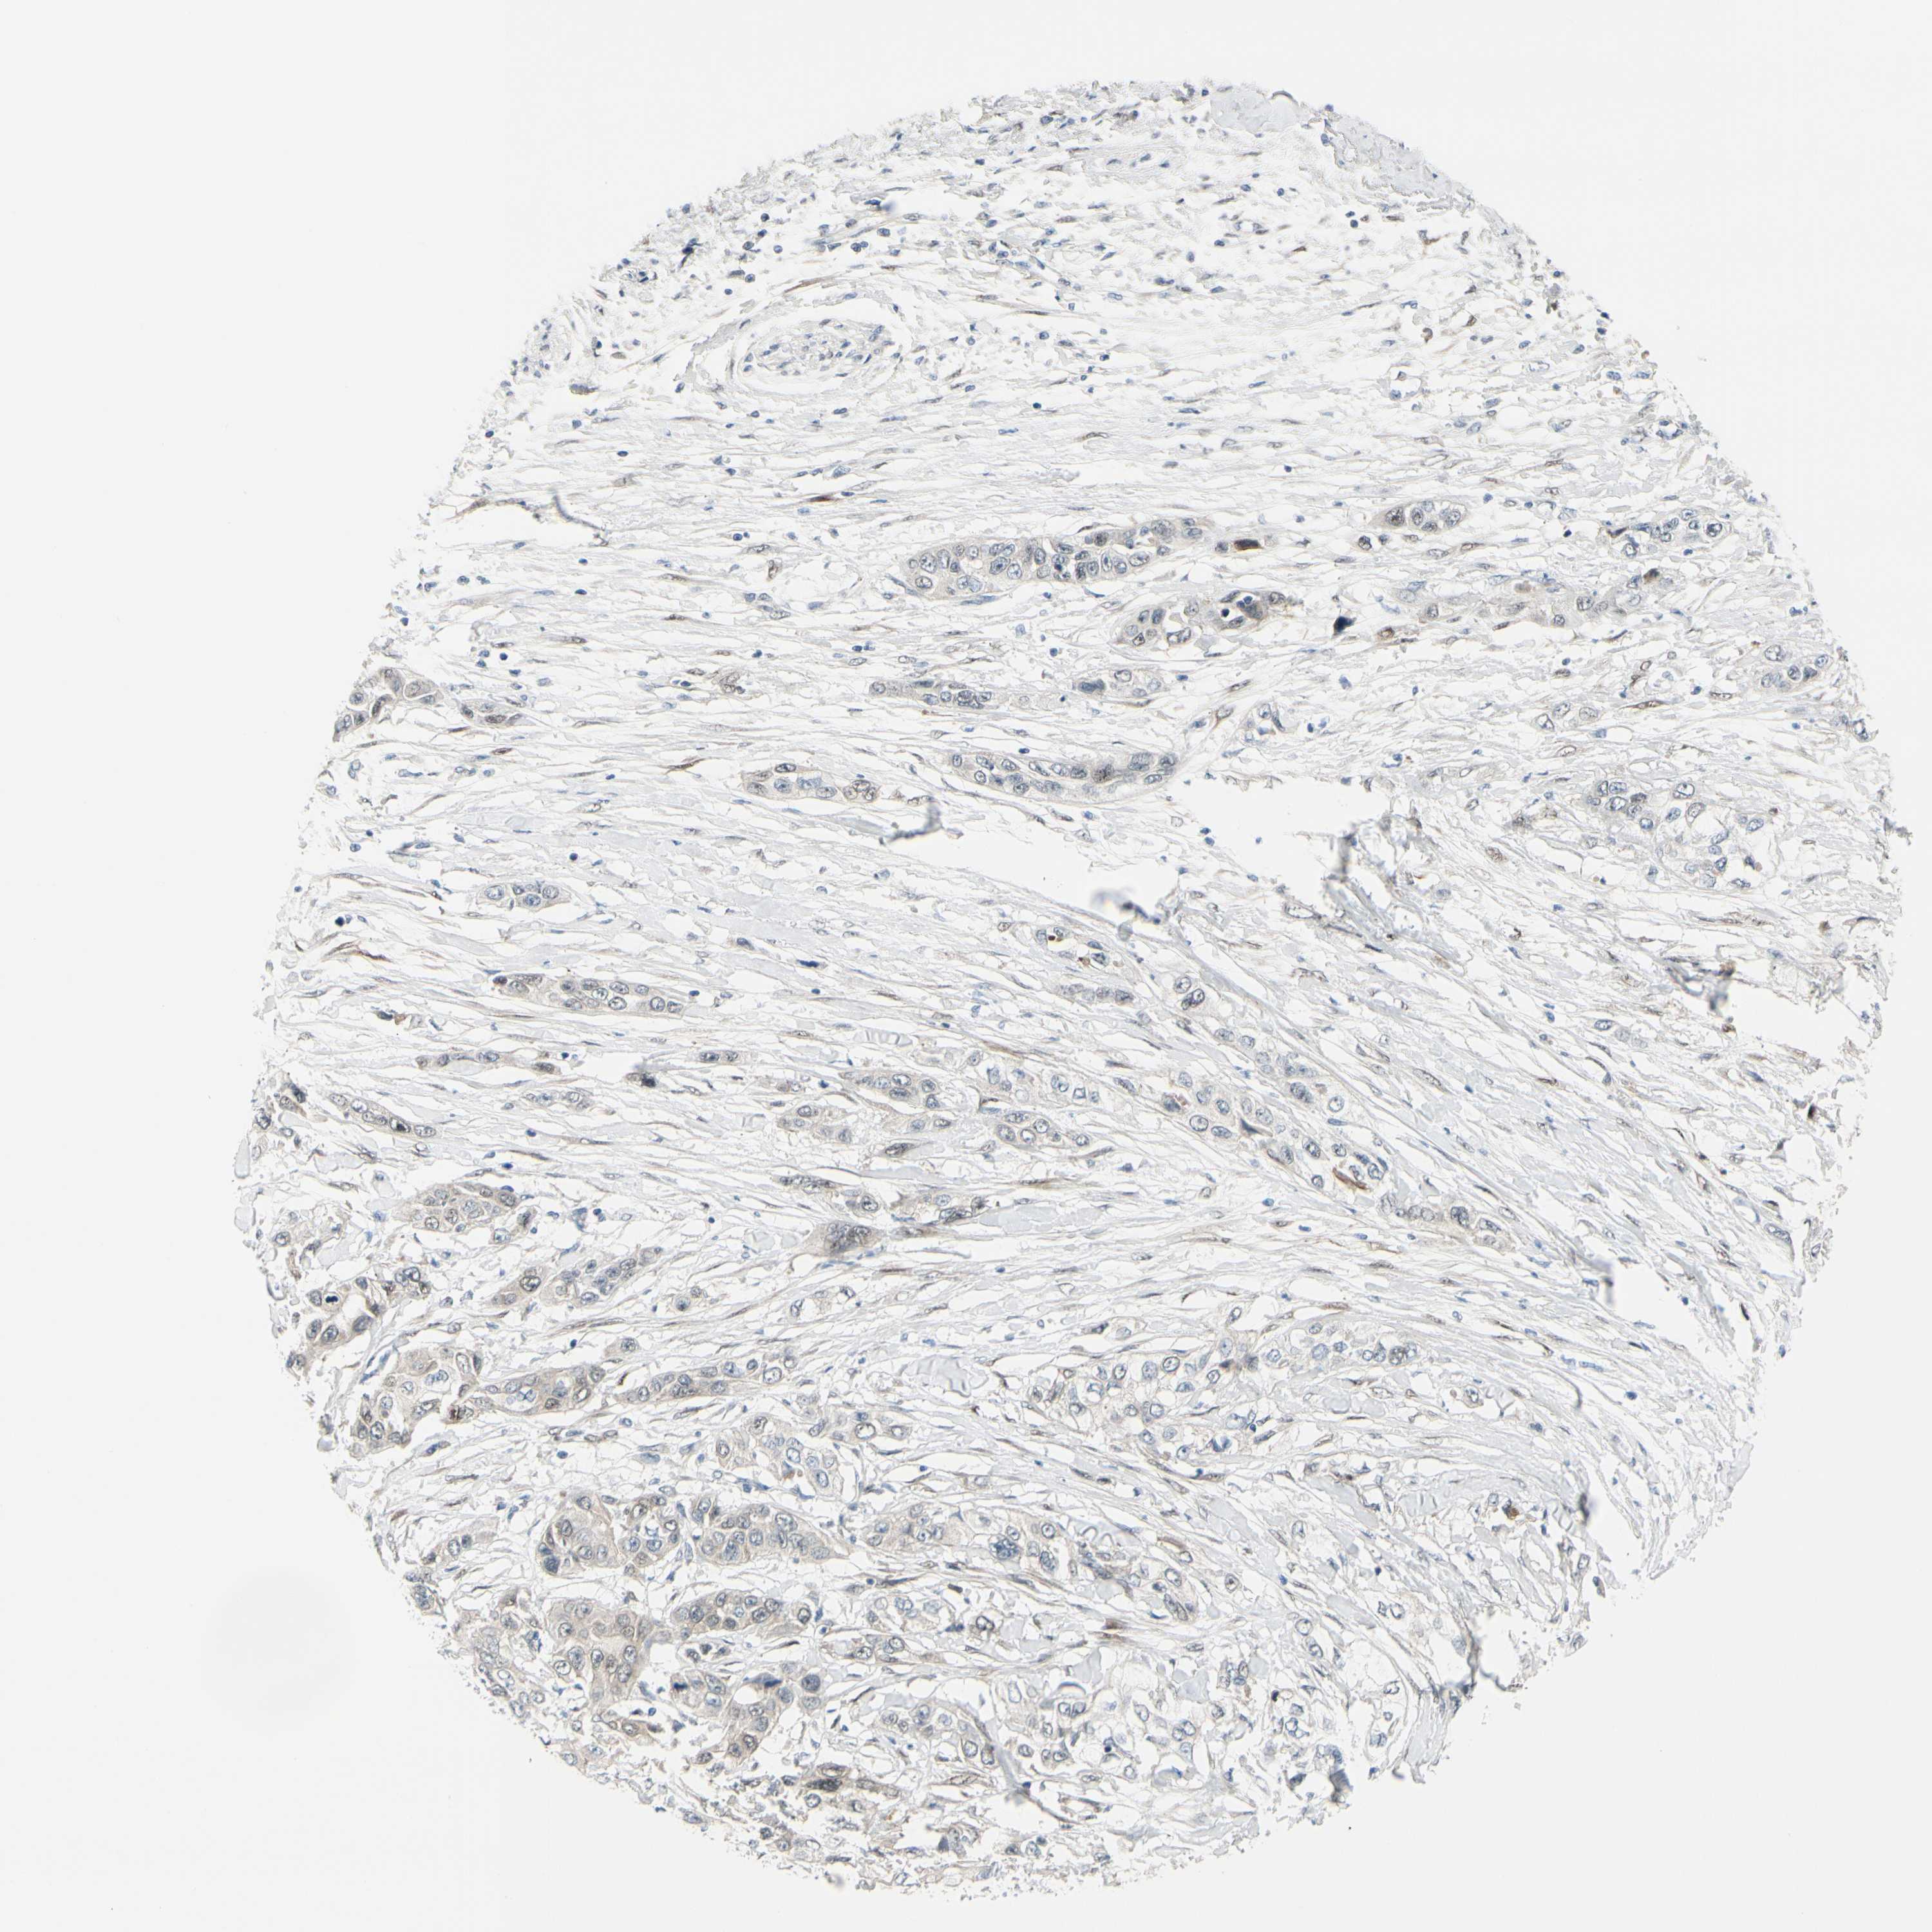

PANCREATIC CANCER - Protein expressioni

A mouse-over function shows sample information and annotation data. Click on an image to view it in a full screen mode. Samples can be filtered based on level of antibody staining by selecting one or several of the following categories: high, medium, low and not detected. The assay and annotation is described here.

Note that samples used for immunohistochemistry by the Human Protein Atlas do not correspond to samples in the TCGA dataset.

Antibody stainingi

Antibody staining in the annotated cell types in the current human tissue is reported as not detected, low, medium, or high, based on conventional immunohistochemistry profiling in selected tissues. This score is based on the combination of the staining intensity and fraction of stained cells.

Each image is clickable and will lead to virtual microscopy that enables deeper exploration of all samples and also displays staining intensity scores, fraction scores and subcellular localization as well as patient and tissue information for each sample.

Antibody HPA005922

Antibody HPA006028

Antibody CAB008368

Adenocarcinoma, NOS

Adenocarcinoma, metastatic, NOS